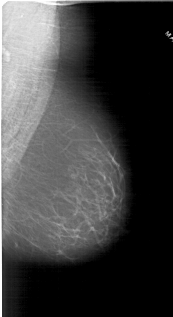

A_1800_1.LEFT_MLO

LEFT_MLO LINES 6691 PIXELS_PER_LINE 3361 BITS_PER_PIXEL 12 RESOLUTION 43.5 OVERLAY